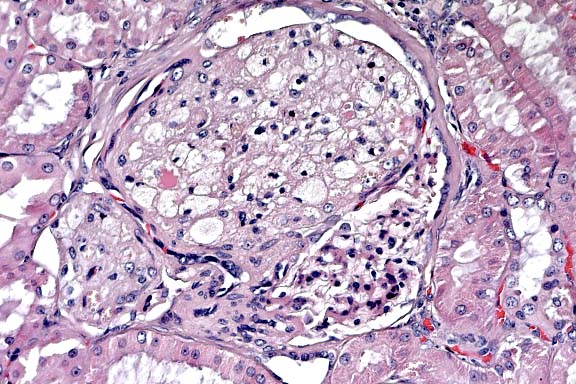

Case 14-4. Kidney. Foamy lipid-containing mesangial cells are expanding the glomerulus. The Bowman's capsule is moderately thickened and fibrotic, forming synechia between the capsule and the glomerular tuft. 20X

AFIP Diagnosis: Kidney: Glomerular lipidosis, segmental to global, diffuse, severe, with moderate periglomerular fibrosis and chronic interstitial nephritis, Beagle, canine.

Conference Note: Conference participants agreed that the extent of the glomerular lipidosis in this case is striking. The clinical chemistry values indicate progressive loss of renal function (markedly increased serum creatinine, mildly increased blood urea nitrogen, proteinuria, and isosthenuria on Day 363). These changes are not anticipated from uncomplicated glomerular lipidosis. Further, glomerular lipidosis would not be expected to cause the chronic inflammatory changes present in this kidney, i.e. lymphoplasmacytic interstitial infiltrates and extensive periglomerular fibrosis. These chronic changes are often seen in mature dogs, and the etiology is usually unknown.